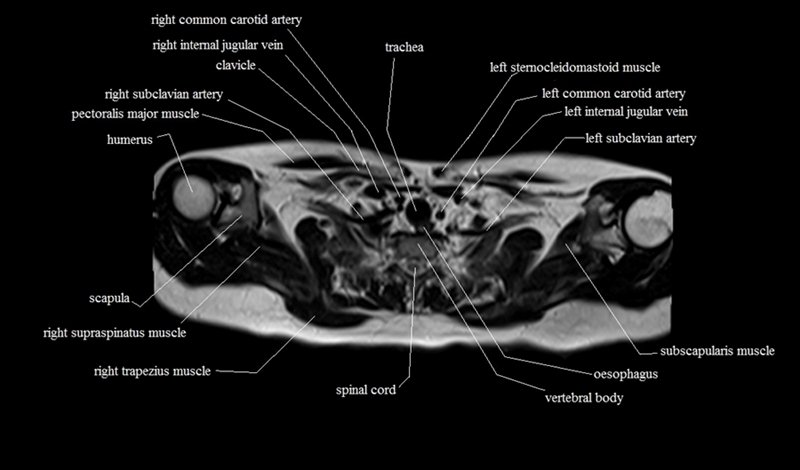

MRI Axial Cross Sectional Anatomy of Chest

This MRI chest (thorax) axial cross sectional anatomy tool is absolutely free to use. Use the mouse scroll wheel to move the images up and down, or alternatively, use the tiny arrows (→) on both sides of the image to navigate through the images. For a more detailed view, double-click the image to view it in full screen, and use the menu in the top right-hand corner to view individual slides or play them in a loop.